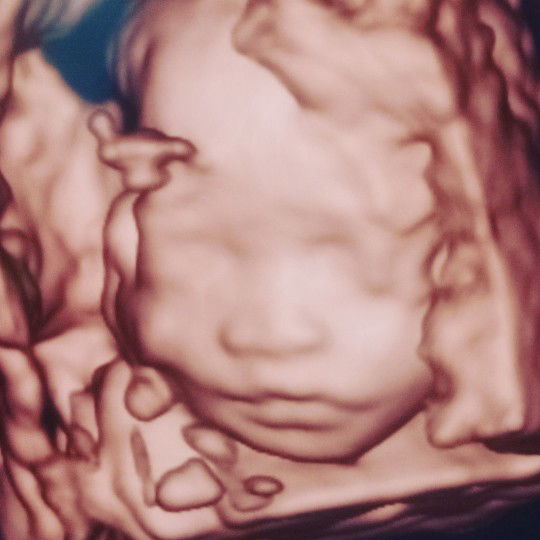

Bun, barusan cek di bidan katanya kandungan aku sdh mengalami pengapuran plasenta saat usia kehamilan 38 week.. itu normal dan membahayakan kandungan gak sih bun ?? Jadi kepikiran soalnya ini baru kehamilan pertama. Minta pendapat nya ya bun... #Nanya #bantusharing #firstbaby